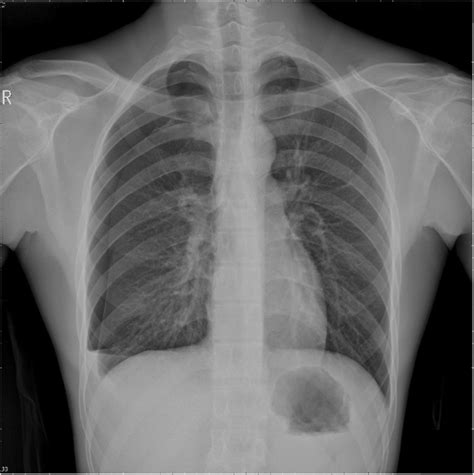

Catamenial pneumothorax: A case report

Catamenial pneumothorax: A case report from www.jpma.org.pk

Why do i need a chest tube? Chest tubes should be removed in a staged manner so as to ensure thatthe air leak into the pleural space has resolved (good consensus). Collapsed lung (pneumothorax)—this occurs when air has built up in the area around the lungs (the pleural space) from a leak in the lung. Thefirst stage requires that a chest radiograph demonstrates completeresolution of the pneumothorax and that there is no clinical evidenceof an ongoing air leak. However, if the leak or pneumothorax is large, then subcutaneous emphysema or an expanding symptomatic pneumothorax is more likely. Feb 01, 2001 · chest tube removal. Ultrasound imaging also may be used to identify a pneumothorax. Common reasons why a chest tube is needed include: